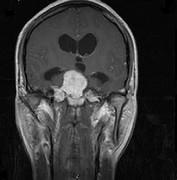

问题 女,32岁,头痛、右侧肢体功能障碍约1年,声间嘶哑,饮水呛咳,请根据所提供图像,选择最可能的诊断()

选项 A.(斜坡)脑膜瘤 B.(斜坡)脊索瘤 C.(斜坡)神经鞘瘤 D.(斜坡)软骨瘤 E.(斜坡)海绵状血管瘤

答案 C